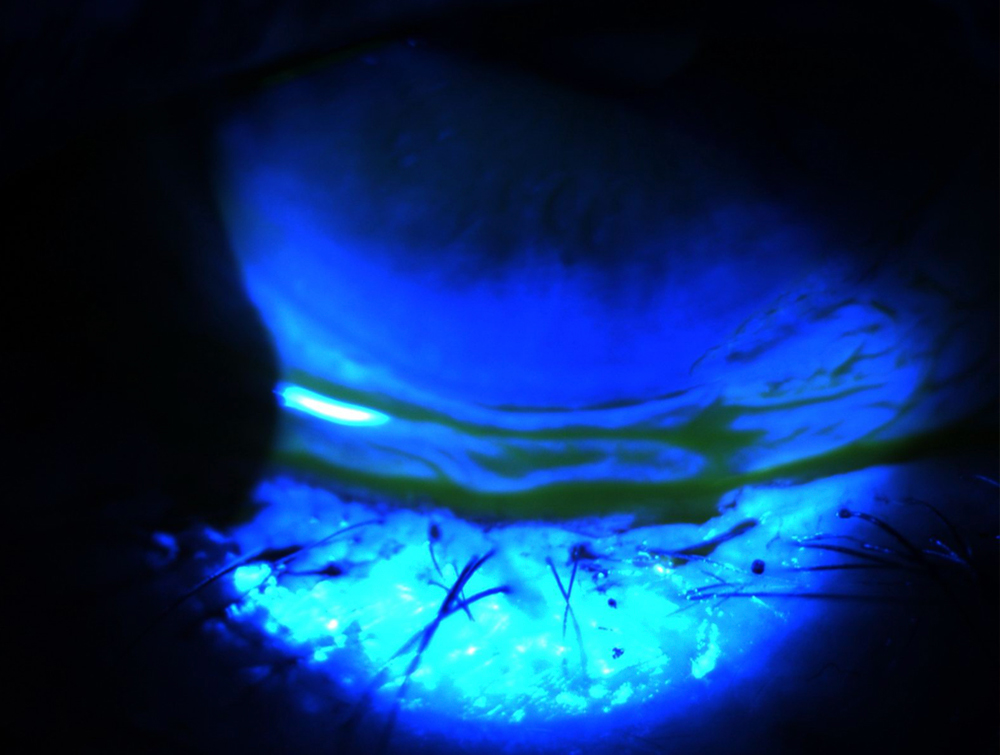

She also said to lift the upper eyelid to look at the superior bulbar conjunctiva. “There are a couple of conditions that we know about from residency but we forget about in real practice. One of them is superior limbic keratoconjunctivitis, also known as SLK. It’s a classic example where there is staining that’s focused on the superior bulbar conjunctiva.” Dr. Khandelwal explained that these patients have more of an inflammatory condition, sometimes with redundancy to the conjunctiva superiorly and occasionally blepharospasm with it. “It’s treated completely differently. Drops only may not help this patient,” Dr. Khandelwal said, explaining that they typically need an anti-inflammatory, an immunomodulator, cauterization, and/or botulinum toxin A to help with the blepharospasm.

Some inflammatory conditions, Dr. Khandelwal noted, can overlap with dry eye but are more significant than “just dry eye.” Other conditions that are more than “just dry eye” include things like limbal stem cell deficiency and ocular cicatricial pemphigoid. Limbal stem cell deficiency can present as a few clock hours of superiorly or subtle corneal neovascularization and a whorl-like staining pattern. Many of these patients are long-time contact lens wearers who have focal limbal stem cell deficiency. Patients with cicatricial pemphigoid often present late, but Dr. Khandelwal said ocular symptoms start somewhere.